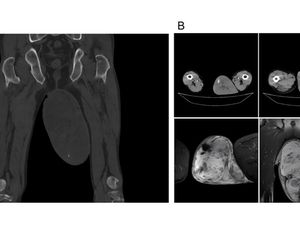

Bongkar Mitos soal Kanker Prostat yang Wajib Diketahui, Ini Faktanya!

Kanker prostat adalah ancaman serius bagi pria. Artikel ini membahas mitos umum dan fakta penting untuk meningkatkan kesadaran serta pentingnya deteksi dini.